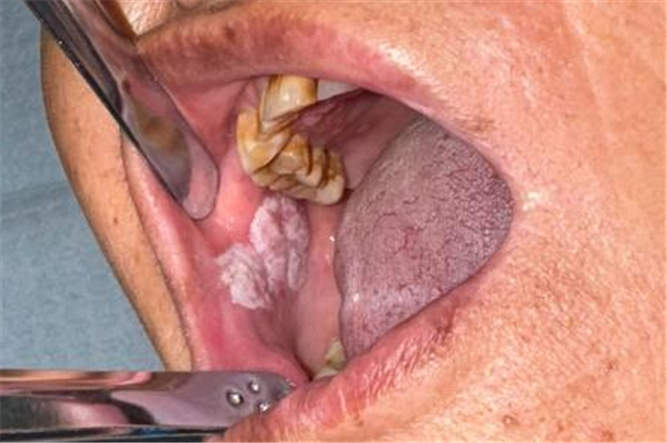

口腔科醫(yī)生接診后,憑借豐富經(jīng)驗(yàn)敏銳察覺(jué)異常:長(zhǎng)期不愈的潰瘍、進(jìn)行性增大的腫物,這些都高度提示“頰癌”可能!

局部活檢病理報(bào)告示:(右頰部)鱗狀上皮不典型增生,鱗狀細(xì)胞癌不除外。結(jié)合臨床特征,均提示這個(gè)腫物很有可能是癌!專家團(tuán)隊(duì)果斷啟動(dòng)多學(xué)科會(huì)診。